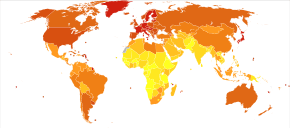

Distribution

As of 2012, pancreatic cancer resulted in 330,000 deaths globally,[2] up from 310,000 in 2010 and 200,000 in 1990.[92] In 2014, an estimated 46,000 people in the US are expected to be diagnosed with pancreatic cancer and 40,000 to die of it.[4] Although it accounts for only 2.5% of new cases, pancreatic cancer is responsible for 6% of cancer deaths each year.[93] It is the seventh highest cause of death from cancer worldwide.[2]

Globally pancreatic cancer is the 11th most common cancer in women and the 12th most common in men.[2] The majority of recorded cases occur in developed countries.[2] People from the United States have an average lifetime risk of about 1 in 67 (or 1.5%) of developing the disease,[94] slightly higher than the figure for the UK.[95] The disease is more common in men than women,[2][4] though the difference in rates has narrowed over recent decades, probably reflecting earlier increases in female smoking. In the United States the risk for African Americans is over 50% greater than for whites, but the rates in Africa and East Asia are much lower than those in North America or Europe. The United States, Central and eastern Europe, and Argentina and Uruguay all have high rates.[2]

Pancreatic cancer is the 10th most common cancer in the UK (around 8,800 people were diagnosed with the disease in 2011), and it is the 5th most common cause of cancer death (around 8,700 people died in 2012).[96]